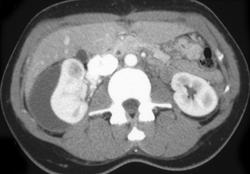

Retroaortic Left Renal Vein